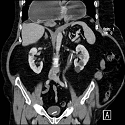

Une forme rare et fulminante de gastrite: la gastrite emphysémateuse

Ammar Mahmoudi, Mezri Maatoug

PAMJ. 2016; 24: 301. Published 09 August 2016